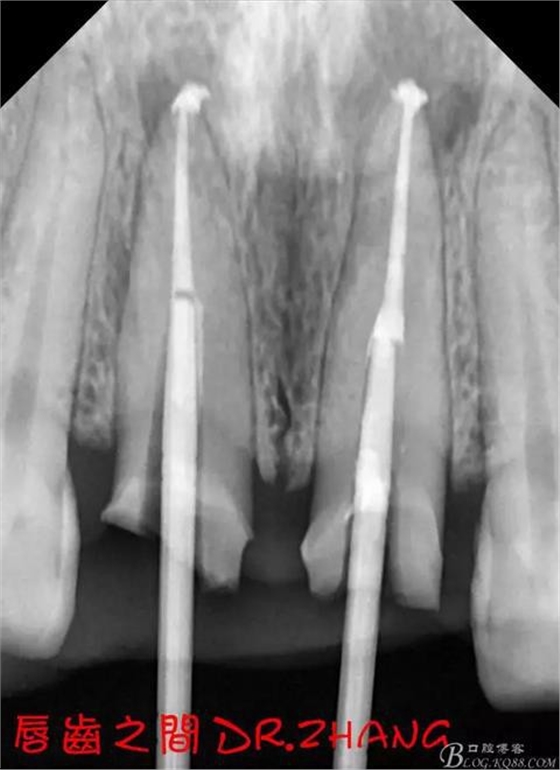

復(fù)診:腫脹明顯消失 患者自訴感覺良好 溝通后決定拆除11 21兩顆烤瓷冠后重新修復(fù) 去冠器直接去冠 去除11根管內(nèi)的充填物 15#K銼疏通根管 11 21根長均為16MM平斷面 薩尼S3系統(tǒng)機擴至2S 期間不斷用氯己定和鹽水交替沖洗 吸潮紙尖干燥根管后06 25#試尖

思博安熱牙膠系統(tǒng)根充 燙斷至根尖三分之一處后纖維樁恢復(fù)牙體組織